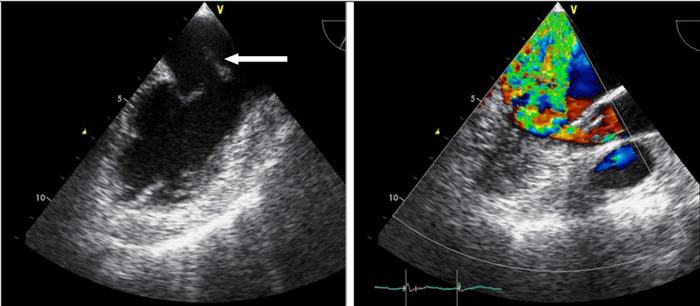

Непрерывноволновая допплер-ЭхоКГ у пациента с клапанным аортальным стенозом.

Слева: слабый допплеровский сигнал и малоинтенсивная граница спектра при нативной регистрации.

Справа: после усиления сигнала при помощи внутривенного введения Левовиста отчетливое выявление пикового градиента, равного 92 мм рт.ст. Трансторакальное исследование потока крови в легочных венах в режиме импульсно-волновой допплер-ЭхоКГ.

Слева: в нативной регистрации слабый допплеровский сигнал и малоинтенсивная граница спектра, не позволяющая провести диагностический анализ.

Справа: после усиления сигнала при помощи внутривенного введения Левовиста отчетливое изображение антеградных и ретроградных диастолических скоростей.

3. Импульсно-волновая допплер-ЭхоКГ. Тот же принцип усиления применим и в режиме импульсно-волнового допплеровского исследования, причем здесь он имеет особенное клиническое значение для регистрации потоков в легочных венах из апикальной позиции, для оценки диастолической функции левого желудочка.